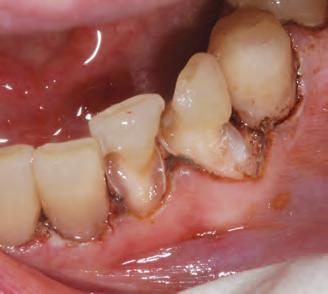

Other types of stains can penetrate into enamel and dentin from the inside, as a consequence of diseases, injury or medical treatment, e.g. congenital, systemic, metabolic, pharmacological, traumatic, or iatrogenic factors such as dental fluorosis, jaundice, tetracycline, and adult minocy-cline stains, porphyria, trauma, and erythroblastosis fetalis. To treat staining from these causes, a medical, in-office whitening system is needed. In many cases such focused whitening may make restorations, veneers or crowns unnecessary or postpone them for a long time.

Opalescence whitening gel is recommended for whitening discolored teeth prior to placement of composite, veneers, and/or crowns. It is effective in breaking down some or all internal tooth discolorations due to factors such as congenital, systemic, pharmacologic, traumatic, etc., as well as aging. It is successful with staining from fluorosis and tetracycline.3,6

Moderate to advanced tetracycline stains. Improvement in 2 weeks. With tetracycline stains, treatment can require 2 to 6 months.1